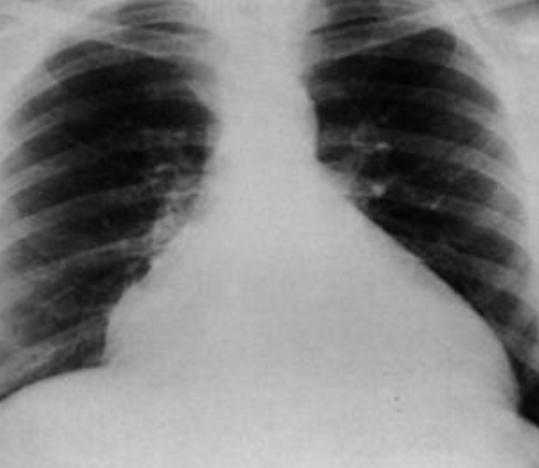

- AP chest film which shows opacification of the middle and lower zones of - (1 .the left lung. The upper border of the opacity is concave

- .This indicates pleural effusion (PE) - (2

- After inserting chest tube, pus was coming out. This means that the PE is - (3 .an Empyema

- .The cause of this empyema is most likely a Bacterial Pneumonia - (4

- The age of the patient is an 8 years which means that the most likely - (5 .organism is Streptococcus Pneumonae